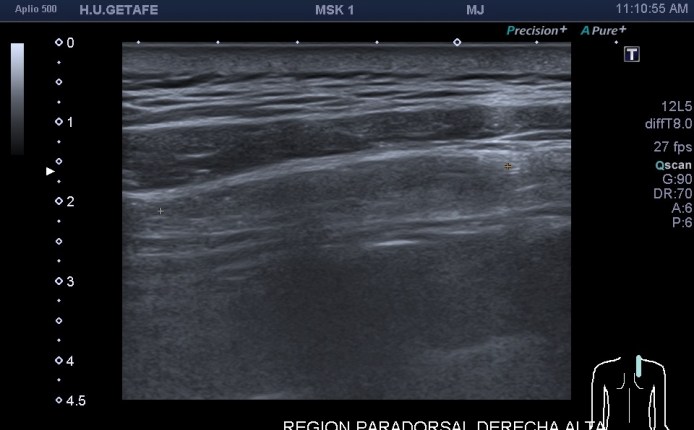

Como hoy quiero que este post sea muy visual y de poca lectura te voy a mostrar los diferentes lugares claves y básicos para que puedas estar atenta en las exploraciones para buscar líquido en estas localizaciones. Primera imagen de normalidad, segunda imagen de «no normalidad» y anatomía y ordenada según la clasificación que has visto un poco más arriba.